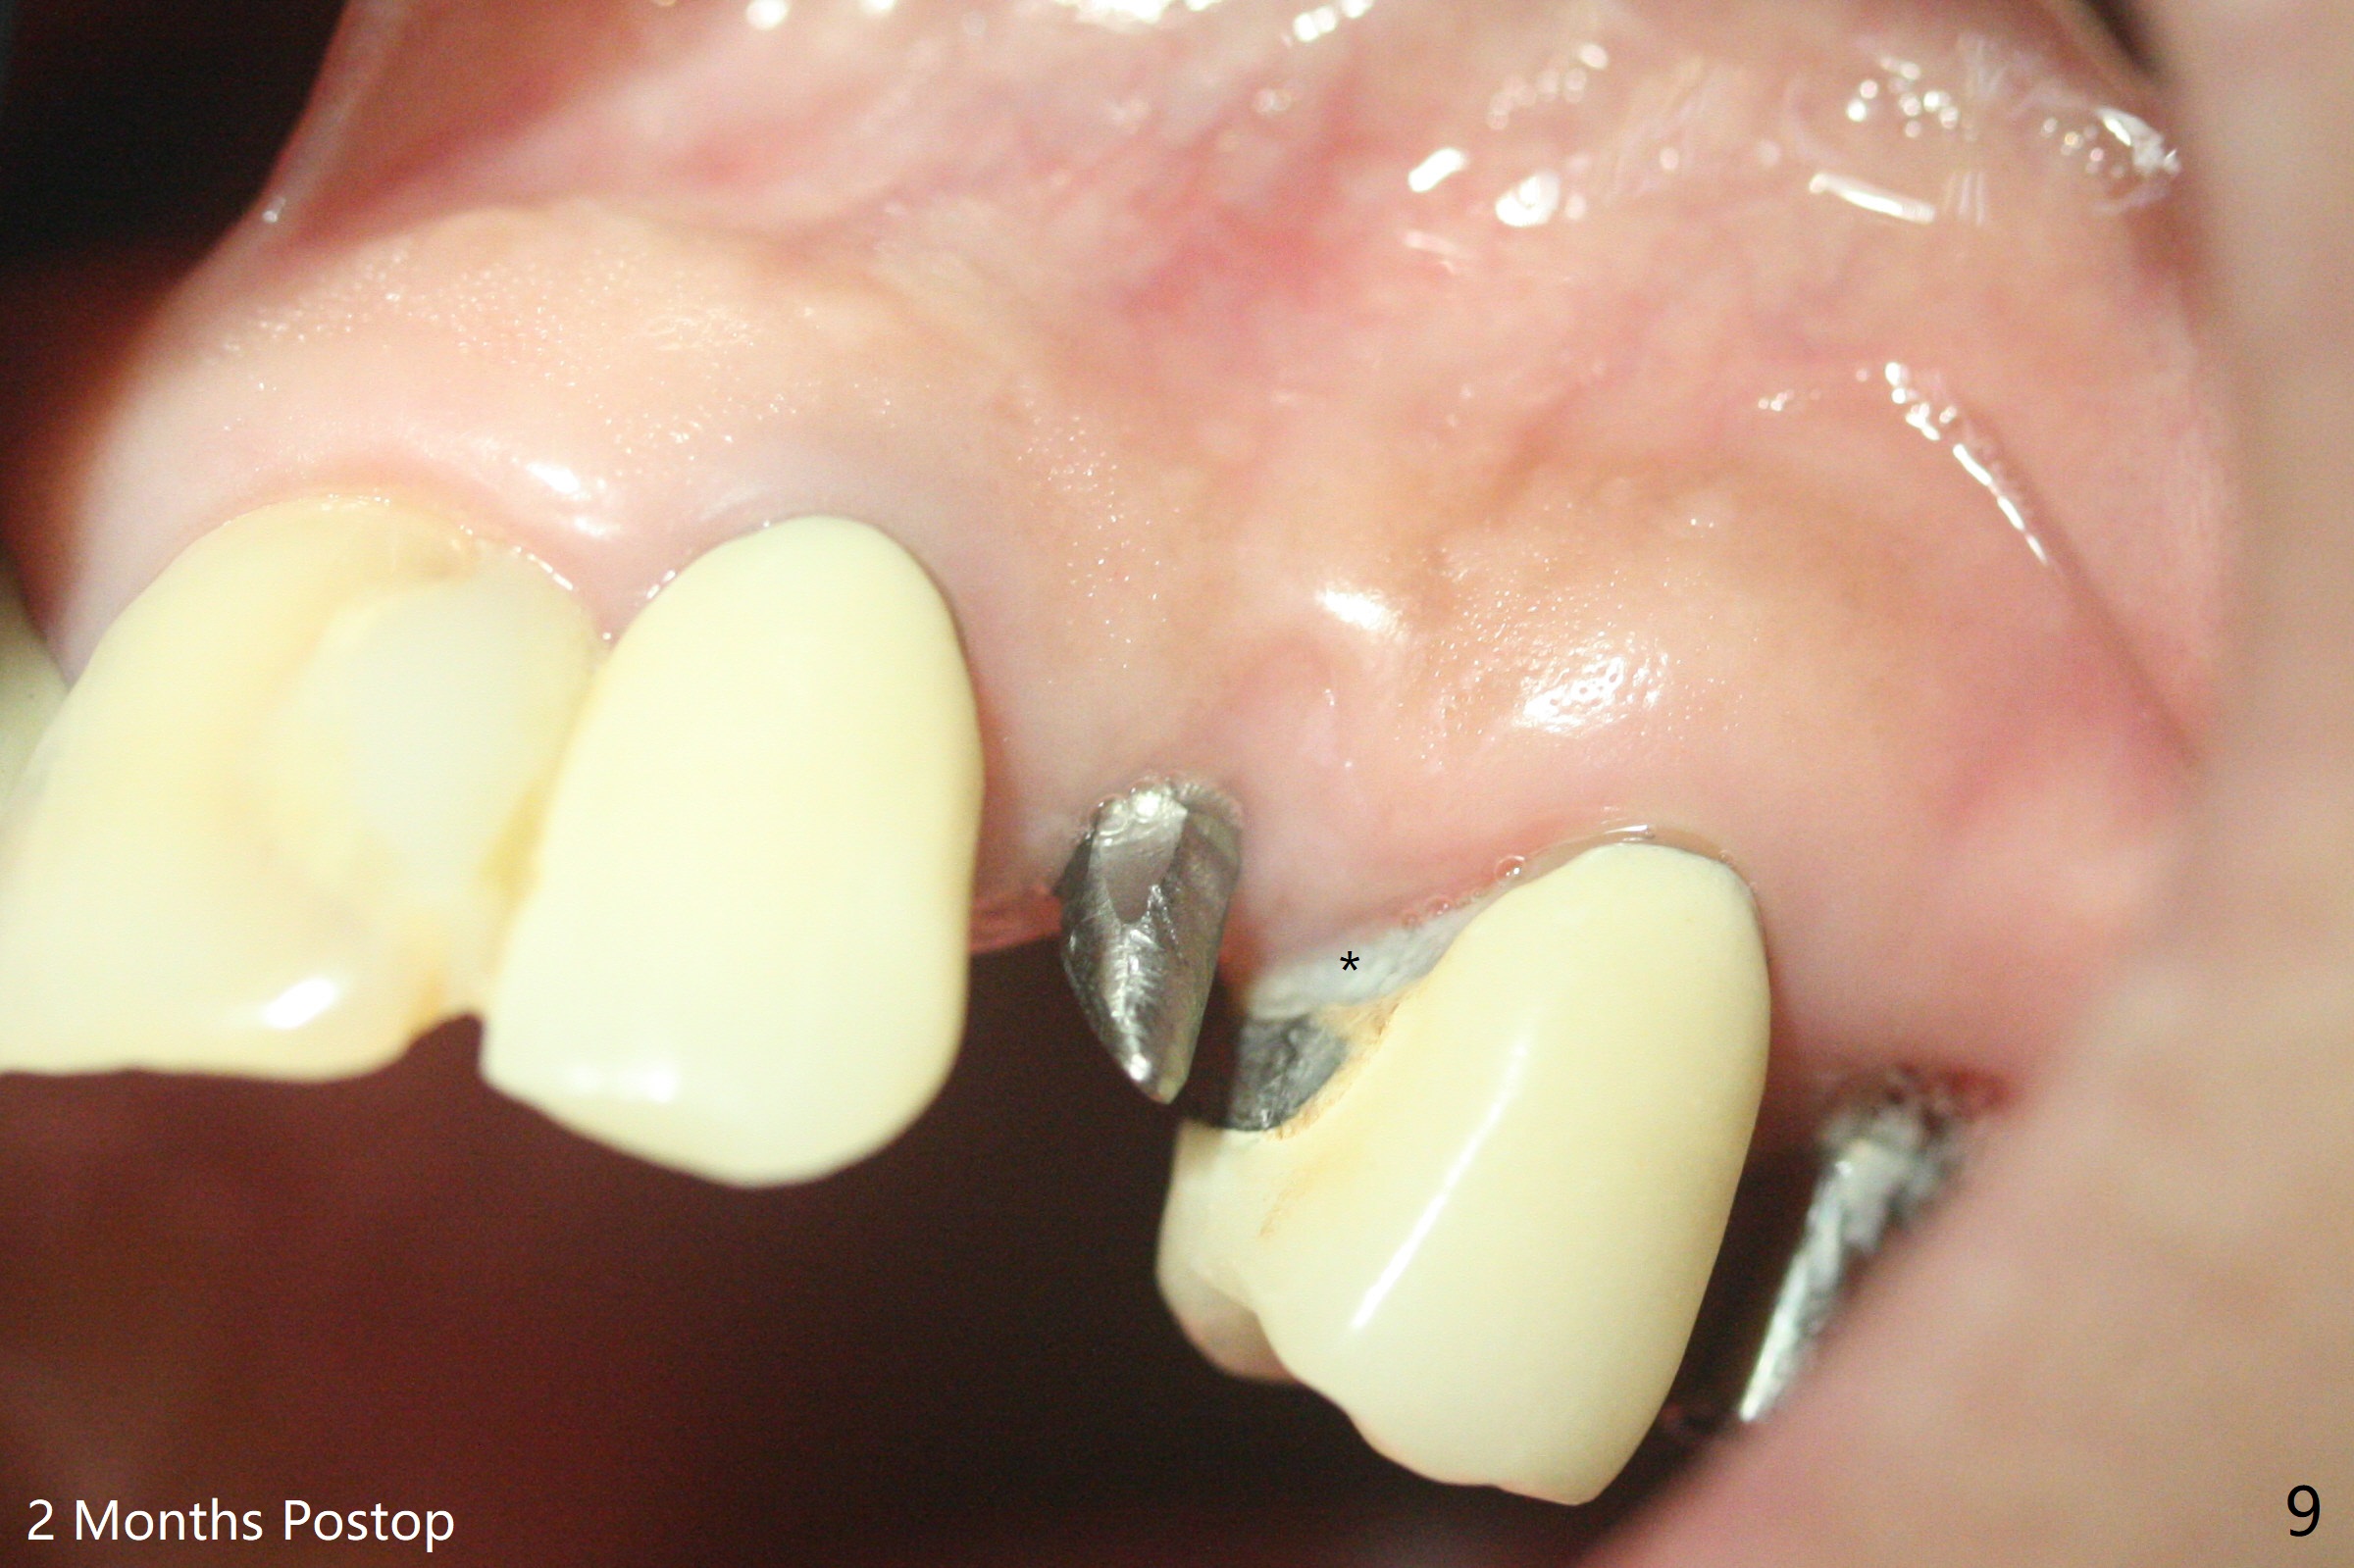

害怕病人局麻药很慢起效,术中身体会动,术中决定减小右下6,7植体直径0.5毫米(与导板设计相比),一旦植体越过牙槽嵴顶骨皮质,稳定性突然减低(图一)。尽管扭力10-15Ncm,为了避免二期手术,放置愈合基台(图二),6基台没有就位(箭头),因为植体种太深了,牙槽骨阻挡(*)基台就位。当取出6基台时,植体一起旋出,重新植入时,就没有种那么深(图三:箭头,与图一,二对比)。由于扭力低,只好放置愈合帽,骨粉(*),GEM Cap(6-9月胶原膜)和牙周胶水。由于导板设计缘故,左上5拔除,种植后,才开始左上3一段式植体植入(图四),5也植入太深(图五),必须放置最小直径最长袖(cuff)的基台(图六),今后导板即刻植牙先不要到达设计深度。术后一周CT显示尖牙植体位于牙槽骨内(图七 (>:腭侧牙槽嵴))。Bone graft fills in the buccal apical defect at #13 one week postop (Fig.8 <). 术后两个月左上3临时牙冠折裂,5松动(图九,十),后者取出衬里,软组织愈合。术后8个月左上3,5取模,右下6 uncover,愈合帽表面覆盖骨质,把7号牙愈合基台放到6号牙上,而7号牙放置4.5x4(4)毫米修复基台,固定牙周敷料,这样6号牙伤口不必缝合。术后8.5个月右下6放置4.5x7.5(4)毫米基台,发现7基台没有就位(图十一:箭头),通过旋转7 基台,终于就位(图十二),螺丝往下移位(与图十一:横线对比),但是基台边缘太低,不利于取模。改用5.5x4(5)毫米UF基台,临床上不能就位,局麻使用5.5毫米Profile Drill后,才能就位(图十三),螺丝下端超越最低螺沟(横线)。